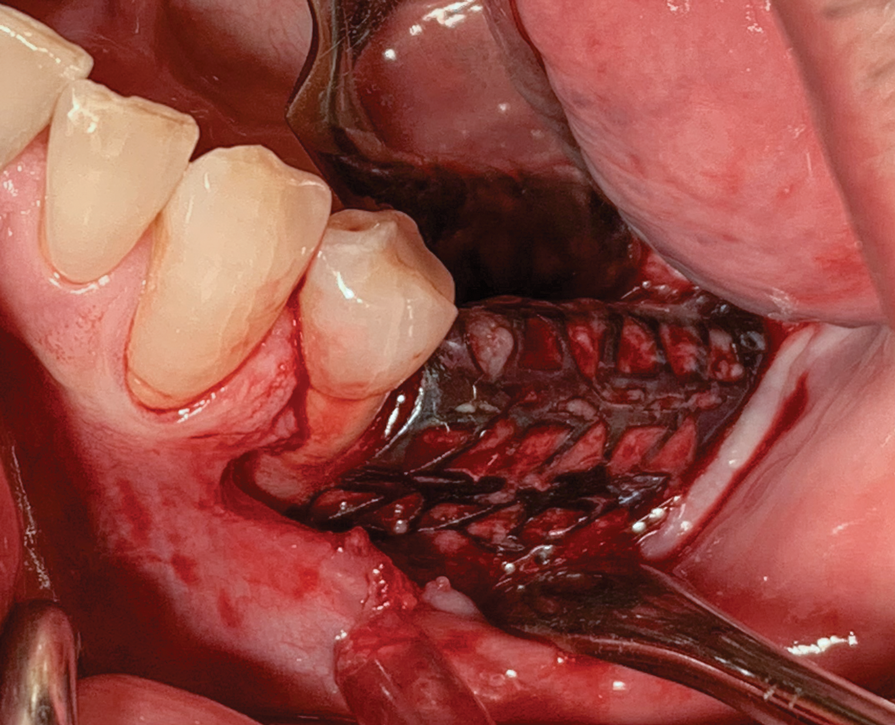

Fig 14. Titanium mesh placed intraorally.

Figure 14

Patient 2, a 50-year-old woman with minor osteoporosis, needed grafting because of  severe atrophy in the right mandible (Siebert class II) (Figure 11 and Figure 12). The  titanium mesh mesh was designed using CAD/CAM tech- nology in the same manner as in Case I. In this case, a mix of autologous and xeno- graft was used. Re-entry time was 8 months. The same protocol was followed as in Case 1 (Figure 13 through Figure 17).